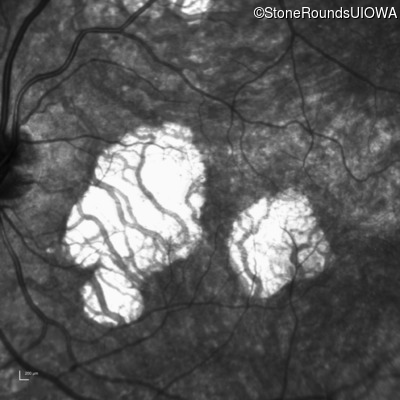

Infrared Fundus Photograph - Right - 20/20 sc

Exemplar